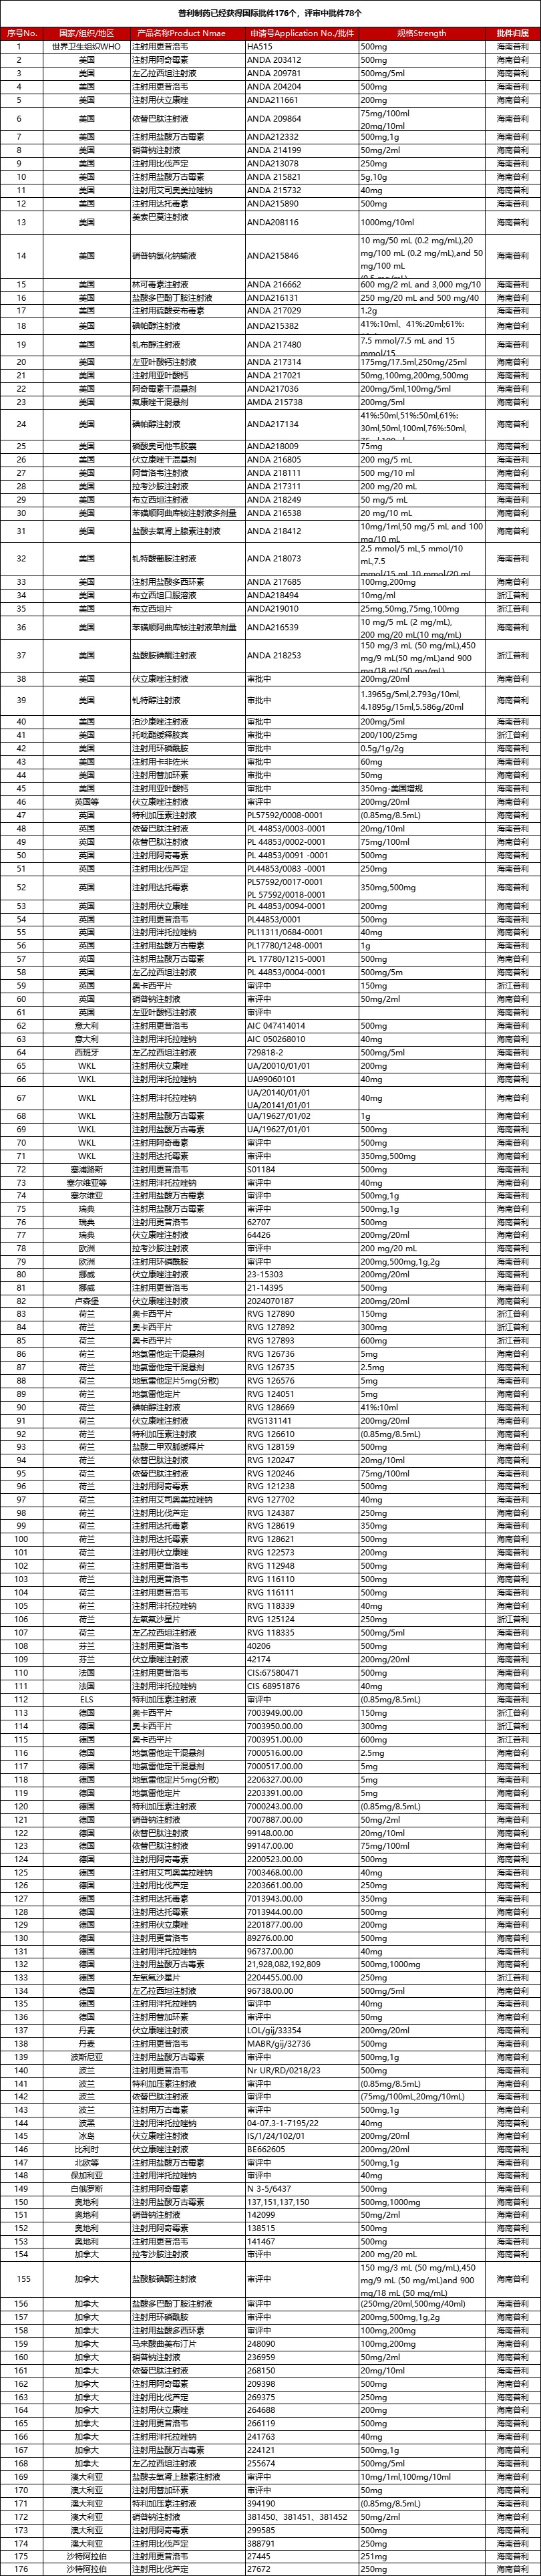

经过不断地学习与积累、创新与发展,普利制药全球化事业迎来了收获期,药品国际化批文爆发式增长。截至目前,普利制药已取得欧美等市场的制剂生产批件176个,其中美国批件36个。2023年,普利制药获得美国批件9个,全国排名第二;2024年年初至今,普利制药已获得美国批件13个,全国排名并列第一;普利制药国际化批文审评中78个,待递交的国际化品种近200个,众多产品正在加速获批中。

另外,普利制药已取得专利技术110余项,其中发明专利90余项;产品批准文号340余个,原料药生产批准及备案文号92个,药用辅料生产批准及备案文号15个,其中多款原料药和要用辅料也都通过了美国FDA与欧盟的认证。